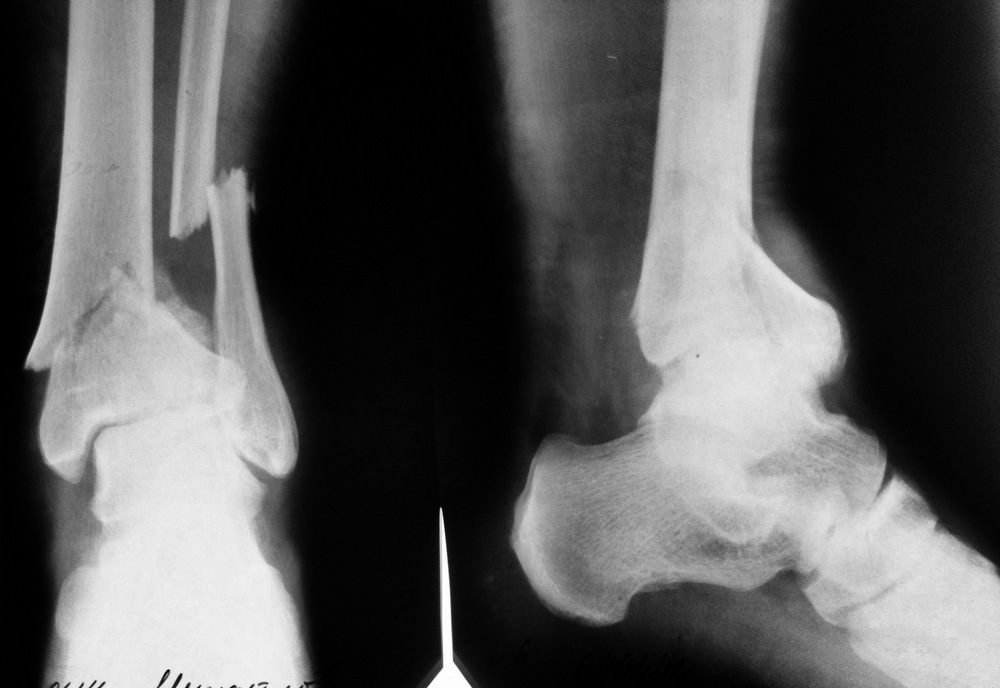

Пациент - мужчина, оперирован по поводу оскольчатого перелома пилона

43-С1 в конце января этого года. Выполнено:

1. ORIF малоберцовой кости 1/3 трубчатой LCP пластиной

2. ORIF пилона антеролатеральной LCP пластиной

В травмпункте, после контрольных рентгенограмм через 8 недель после

операции рекомендована ходьба с тростью и практически полной нагрузкой.

Через 2 недели после начала ходьбы произошел перелом импланта. Доктор в

травмпункте объяснил это не качественностью пластины.

1. На фоне замедленно консолидирующегося перелома (контроль через 8

недель) разрешена практически полная нагрузка на конечность. Кстати,

пациент достаточно крупный мужчина;